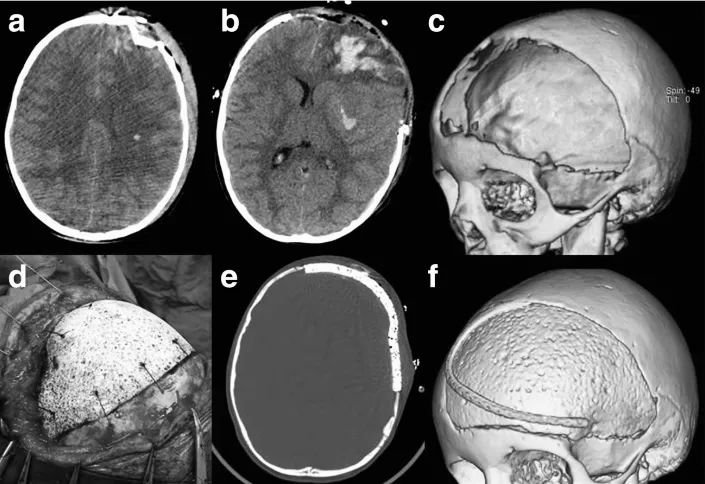

在骨科领域,尤其是颅骨修复中,引入陶瓷材料是基于生物模仿学的理念,旨在恢复颅骨的完整性,而不仅仅是简单地重建。羟基磷灰石(HA)因其与人体骨骼相同的矿物质成分而著称,因此据称具有成骨传导性和成骨诱导性。尽管骨水泥的使用在短期内并发症发生率较低,但在长期中,这一比例显著上升,尤其是骨折、皮肤侵蚀和感染,最高可达 75% 的病例。为了克服这些限制并增强 HA 的生物仿生特性,通过改变其结构,特别是孔隙率,取得了一定进展。定制 HA 植入物显示出的大孔隙应有助于其骨整合(图 5 和图 6)。

图 5:一名 6 岁女童遭受严重头部损伤(a),接受减压性颅骨切除术(b、c)。采用定制大孔羟基磷灰石(HA)进行颅骨修复(d - f)。